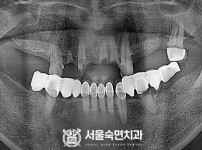

임플란트-전후사진4

치과를-선택할-때-꼭-확인하세요-서울숙면치과-임플란트-전후사진